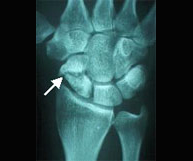

The scaphoid bone is the most common fracture of the carpal bones after falls with an outstretched hand. This is a characteristic injury in sports such as motorcycling, cycling and skateboarding where they can suffer high speed injuries. The pain is located along the axis of the thumb and the tenderness in the wrist area (snuffbox) is extreme. Displaced fractures usually required surgically stabilization through the introduction of percutaneous intraosseous screws.